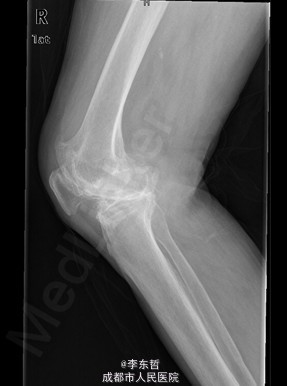

患者女,74岁,因“双膝疼痛20年,加重伴行走困难8年”入院。患者诉20年前开始出现双膝关节疼痛,负重行走、下楼时疼痛加重,休息后可缓解,尚可下蹲。自行购买止痛药口服,关节腔内注射玻璃酸钠、理疗等处理,疼痛时有缓解。但症状反复发作。8年前疼痛加重且行走困难,扶拐行走仅能坚持约10余米,上下楼梯艰难,下蹲不能,以左侧为重。遂来院就诊。

查体:跛行步态,双膝关节屈曲内翻畸形,双膝内侧间隙压痛,双膝髌股关节间隙压痛,左膝伸-20°,屈110°内翻10°。右膝伸-20°,屈110°内翻10°,双膝屈伸活动时髌骨下摩擦感(+)。 辅助检查:X片示双侧髌股关节内侧间室变窄,关节边缘骨赘增生,软骨下骨硬化。

入院诊断:1、左膝骨关节炎伴屈曲内翻畸形; 2、右膝骨关节炎伴屈曲内翻畸形; 诊疗计划:1、向患者及家属交待病情及注意事项。2、向上级医生汇报患者病情。3、完善相关术前检查;4、择期手术。